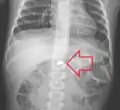

AP X ray showing a 9mm battery in the intestines

Lateral X ray showing a 9mm battery in the intestines